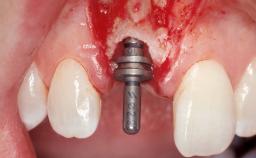

Late Flapless Placement of an Implant in a Maxillary Left Central Incisor Site

A 39-year-old male patient presented with a chief complaint of discomfort and gingival discoloration around his maxillary left central incisor. He was in good general health and was a non-smoker. His past dental history was significant because of the traumatic fracture of tooth 21 in a sporting accident at age 13. Initial dental treatment included endodontic therapy and a full-coverage restoration. The patient became symptomatic 5 years later, when structural failure of the tooth resulted in the dislodgment of the crown. Endodontic retreatment, apical surgery, and post-and-core restoration were performed.

Type of Implants One-Piece

Bone Augmentation Horizontal|Staged

Placement Protocol Early or late implant placement